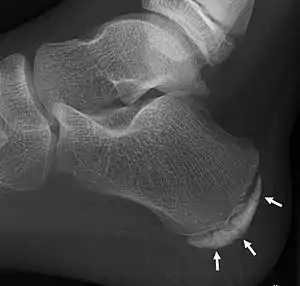

| X-ray of the foot of an 11-year-old child,showing sclerosis and fragmentation of the calcaneal apophysis. This is a sign of low sensitivity and specificity of Sever's disease, because those with Sever's disease may not have it, and this appearance is also present in feet without pain. | |

Children with calcaneal apophysitis commonly complain of pain at the back of the heel. This pain increases with jumping and some running sports. Sometimes, the pain makes children limp and may result in poor sports performance or them not wanting to participate in some sports. The back of the heel is never swollen or red, unless there has been shoe rubbing. When the back of the heel is squeezed from the inside and outside, children with calcaneal apophysitis will report pain. Foot radiographs are not needed to diagnose calcaneal apophysitis as the growth plate can look similar with or without pain. Health professionals should only refer for imaging when the symptoms don't match with the usual presentation or there has been an injury that has resulted in heel pain. Therefore, the diagnosis of Sever's disease is primarily from history and physical assessment.[5]